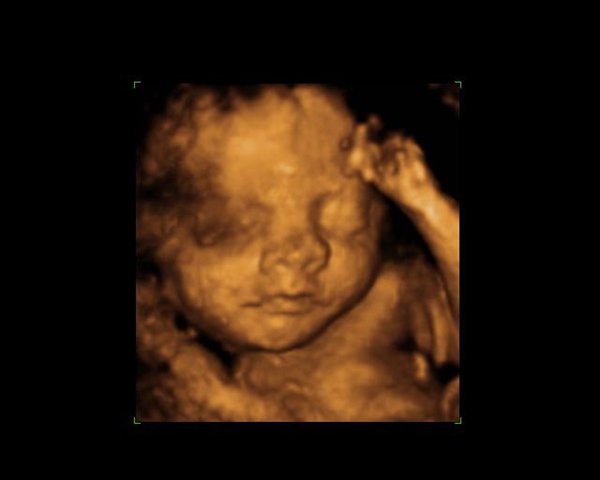

jeg tror ikke barnet er for stort efter uge 30, men det kommer måske an på hvor stor barnet er. Da jeg blev 3D/4D scannet vejede den lille ca. 1761 gram, mit lille problem var bare at vores bebse lå med hovedet godt ned allerede, så hun var nød til at scanne mig imens jeg lå på siden, for lige at få ansigtet frem

Men vi fik fine billeder med hjem